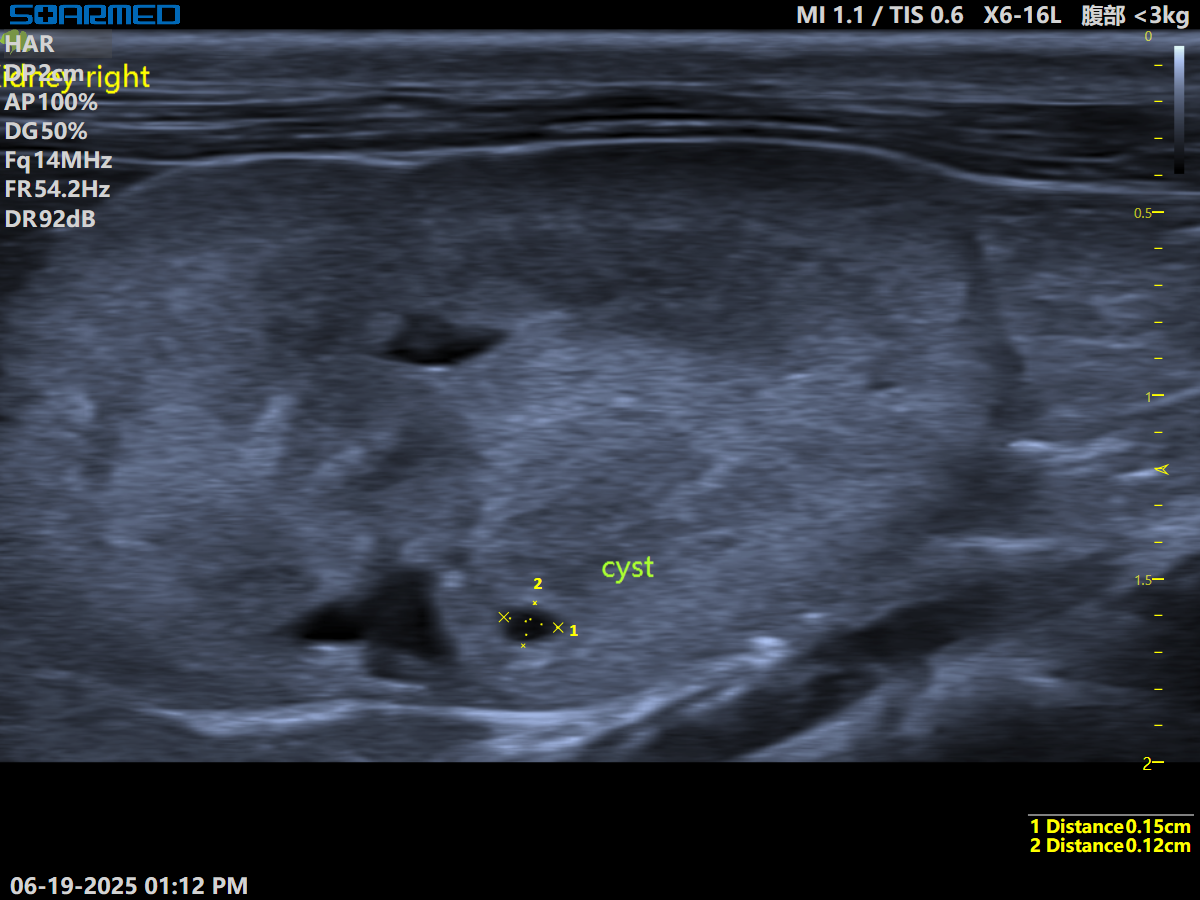

RK.png